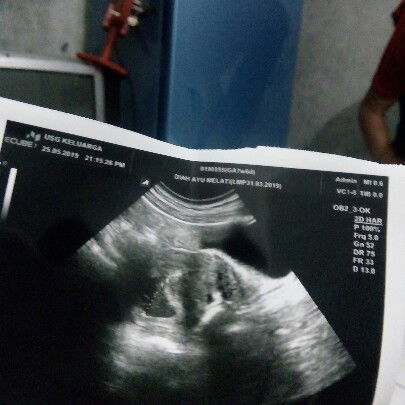

bundaa , kan aku trakhir mens tgl 1 april 2019 menurut hitungan bidan usia kehamilan sudah 8 minggu , tapi aku baru saja USG kata dokternya usianya baru 6 minggu .. menurut bunda2 hitungan ikut yang mana ya ? soalnya baru hamil pertama ?tq..

usg bunda